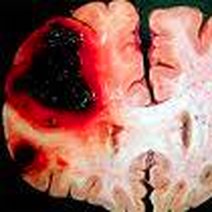

脑水肿是指脑内水分增加、导致脑容积增大的病理现象,是脑组织对各种致病因素的反应。可致颅内高压,损伤脑组织,临床上常见于神经系统疾病,如颅脑外伤,颅内感染(脑炎,脑膜炎等),脑血管疾病,颅...

脑水肿是脑内水分异常增多致脑容积增大源于液体平衡失衡,血脑屏障受损等引发血管源性脑水肿(多由脑肿瘤、脑外伤等致血脑屏障破坏,病变在白质范围较广),脑缺血缺...

脑水肿的原因有哪些?有问必答网脑水肿疾病查询频道为您解答脑水肿是怎么引起的,1、颅脑损伤各类颅脑损伤,直接或间接地造成脑挫裂伤都能引起脑水肿,并发颅内血肿,使局部脑组织受压也可引...